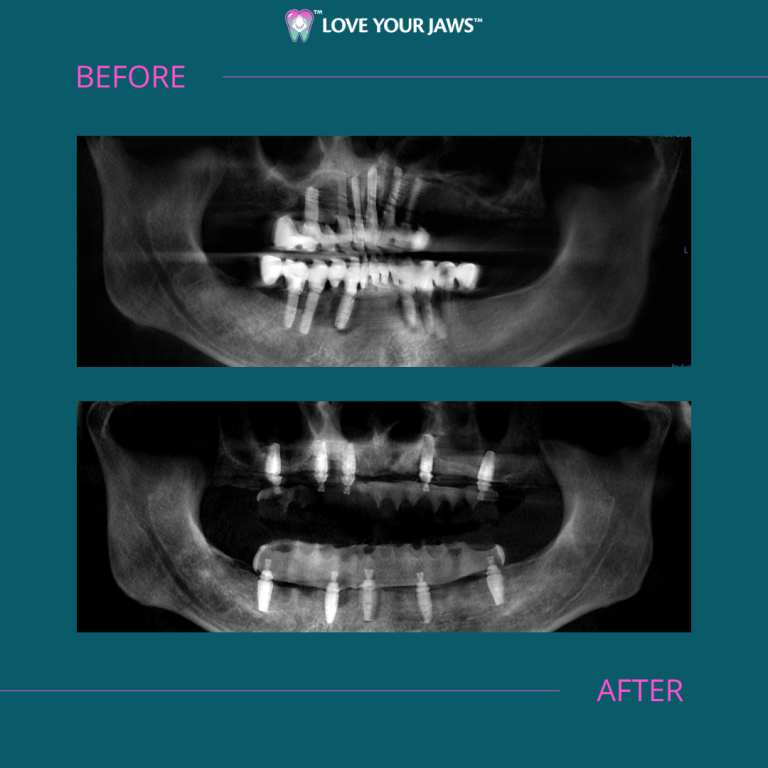

Uno de nuestros casos más destacados fue el de un paciente internacional con implantes dentales de arcada completa fallidos procedentes de Europa. El paciente acudió a nuestro centro quirúrgico en South Miami con complicaciones graves, incluidas infecciones mandibulares y una salud bucodental comprometida debido a implantes mal colocados. Su situación era crítica, lo que afectaba a su capacidad para comer, hablar y vivir con comodidad.

En Love Your Jaws, restauramos la función y la salud retirando los implantes fallidos, eliminando las infecciones mandibulares y colocando implantes de alta calidad para una reconstrucción de arcada completa “All-on-X” con carga protésica inmediata. Esta técnica avanzada nos permitió reconstruir toda la arcada dental con un número mínimo de implantes, proporcionando funcionalidad y estética inmediatas. ¿El resultado? Una sonrisa radiante y segura, y una calidad de vida totalmente recuperada.

Este caso subraya nuestra experiencia en el manejo de casos complejos de implantes dentales, incluso en pacientes que han sufrido contratiempos en otros lugares. Nuestro centro quirúrgico combina tecnología de vanguardia con una atención compasiva para ofrecer resultados excepcionales.

Para nuestro paciente internacional, el procedimiento “All-on-X” no solo resolvió sus problemas de salud, sino que también le proporcionó una sonrisa bonita y funcional que transformó su vida diaria. Historias como la suya nos inspiran a seguir ofreciendo una atención de primer nivel en Love Your Jaws.